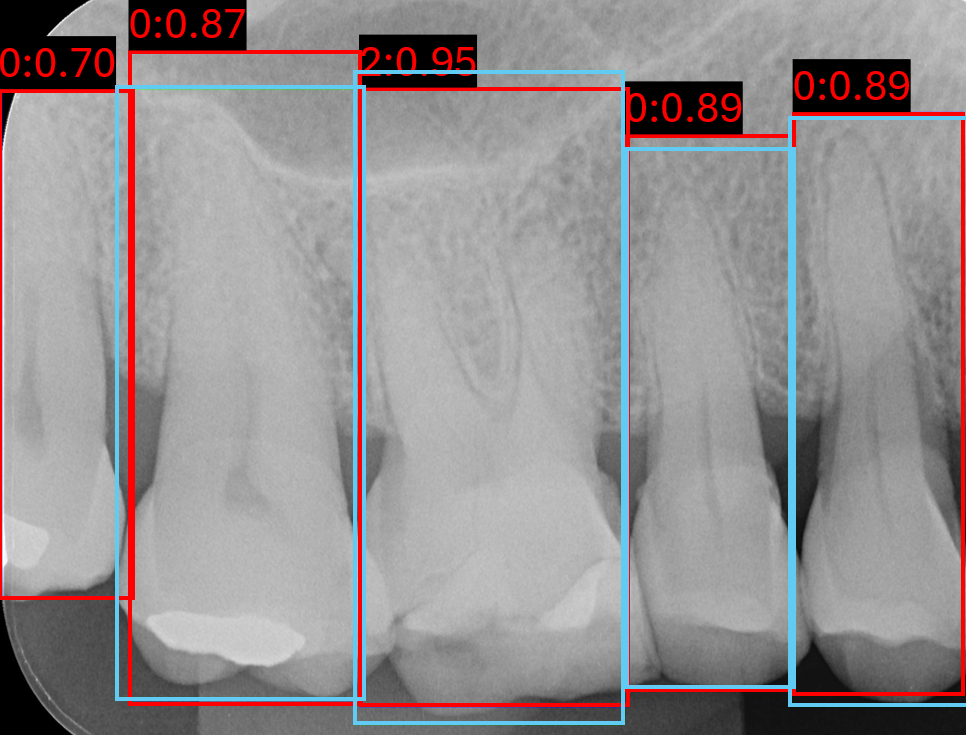

3.2.2 Keypoint Detection Results

Keypoint localisation was evaluated using PRCKPRCK across multiple thresholds, with and without post-processing in Table 5. At the coarse threshold PRCK0.5PRCK^{0.5}, YOLOv8 outperforms all other models, achieving 0.9120.912(±0.026\pm 0.026) on the validation set and 0.9000.900(±0.029\pm 0.029) on the external set, reflecting strong robustness against localisation error. In contrast, performance at the strict threshold PRCK0.05 indicates HRNet’s advantage in fine-grained precision compared to its lower generalised precision at lower thresholds, where it achieved the highest scores of 0.3750.375(±0.027\pm 0.027) on the validation set and 0.4050.405(±0.029\pm 0.029) on the external set.

Post-processing consistently improved strict-threshold PRCK0.05PRCK^{0.05} performance across models. For example, YOLOv8 increased from 0.3680.368(±0.059\pm 0.059) to 0.4040.404(±0.048\pm 0.048) on the validation set and from 0.3090.309(±0.083\pm 0.083) to 0.3560.356(±0.086\pm 0.086) on the external set. However, these gains in fine localisation were often accompanied by reductions at broader thresholds, PRCK0.25PRCK^{0.25} and PRCK0.5PRCK^{0.5}.

Analysing the validation set, in Figure 8, qualitatively shows that raw predictions rarely coincide with anatomically correct locations, often being detected within the tooth interior or entirely outside its boundary. Post-processing substantially improves localisation in most cases, shifting keypoints towards plausible mesial and distal edges, as shown in Figure 8(a) and 8(d). However, this refinement is heavily dependent on the quality of the raw detections. When predictions are excessively noisy, post-processing can amplify errors, relocating keypoints to implausible locations such as the crown or furcation apex, as seen in Figure 8(g) and Figure 8(h). This further explains the observed quantitative increase for prck0.05prck^{0.05}, but declination at more lenient thresholds, since small adjustments improve low-tolerance metrics, yet fail to increase high-tolerance thresholds.

Refer to caption

(a) Image 120 DeepPose

(b) Image 120 HRNet

(c) Image 120 RTMPose

(d) Image 120 YOLOv8

(e) Image 171 DeepPose

(f) Image 171 HRNet

(g) Image 171 RTMPose

(h) Image 171 YOLOv8

Figure 8: Six validation images with overlay keypoint results, where red points are the raw keypoint predictions and green points are the post-processed keypoints.

Further analysis of post-processing PRCKPRCK metrics at a range of thresholds in Figure 9, all models except HRNet show slightly reduced 0.50.5-0.20.2 threshold performance for post-processed keypoints compared to no post-processing. However, post-processed and non-post-processed performance inverts between a threshold of 0.20.2-0.10.1.